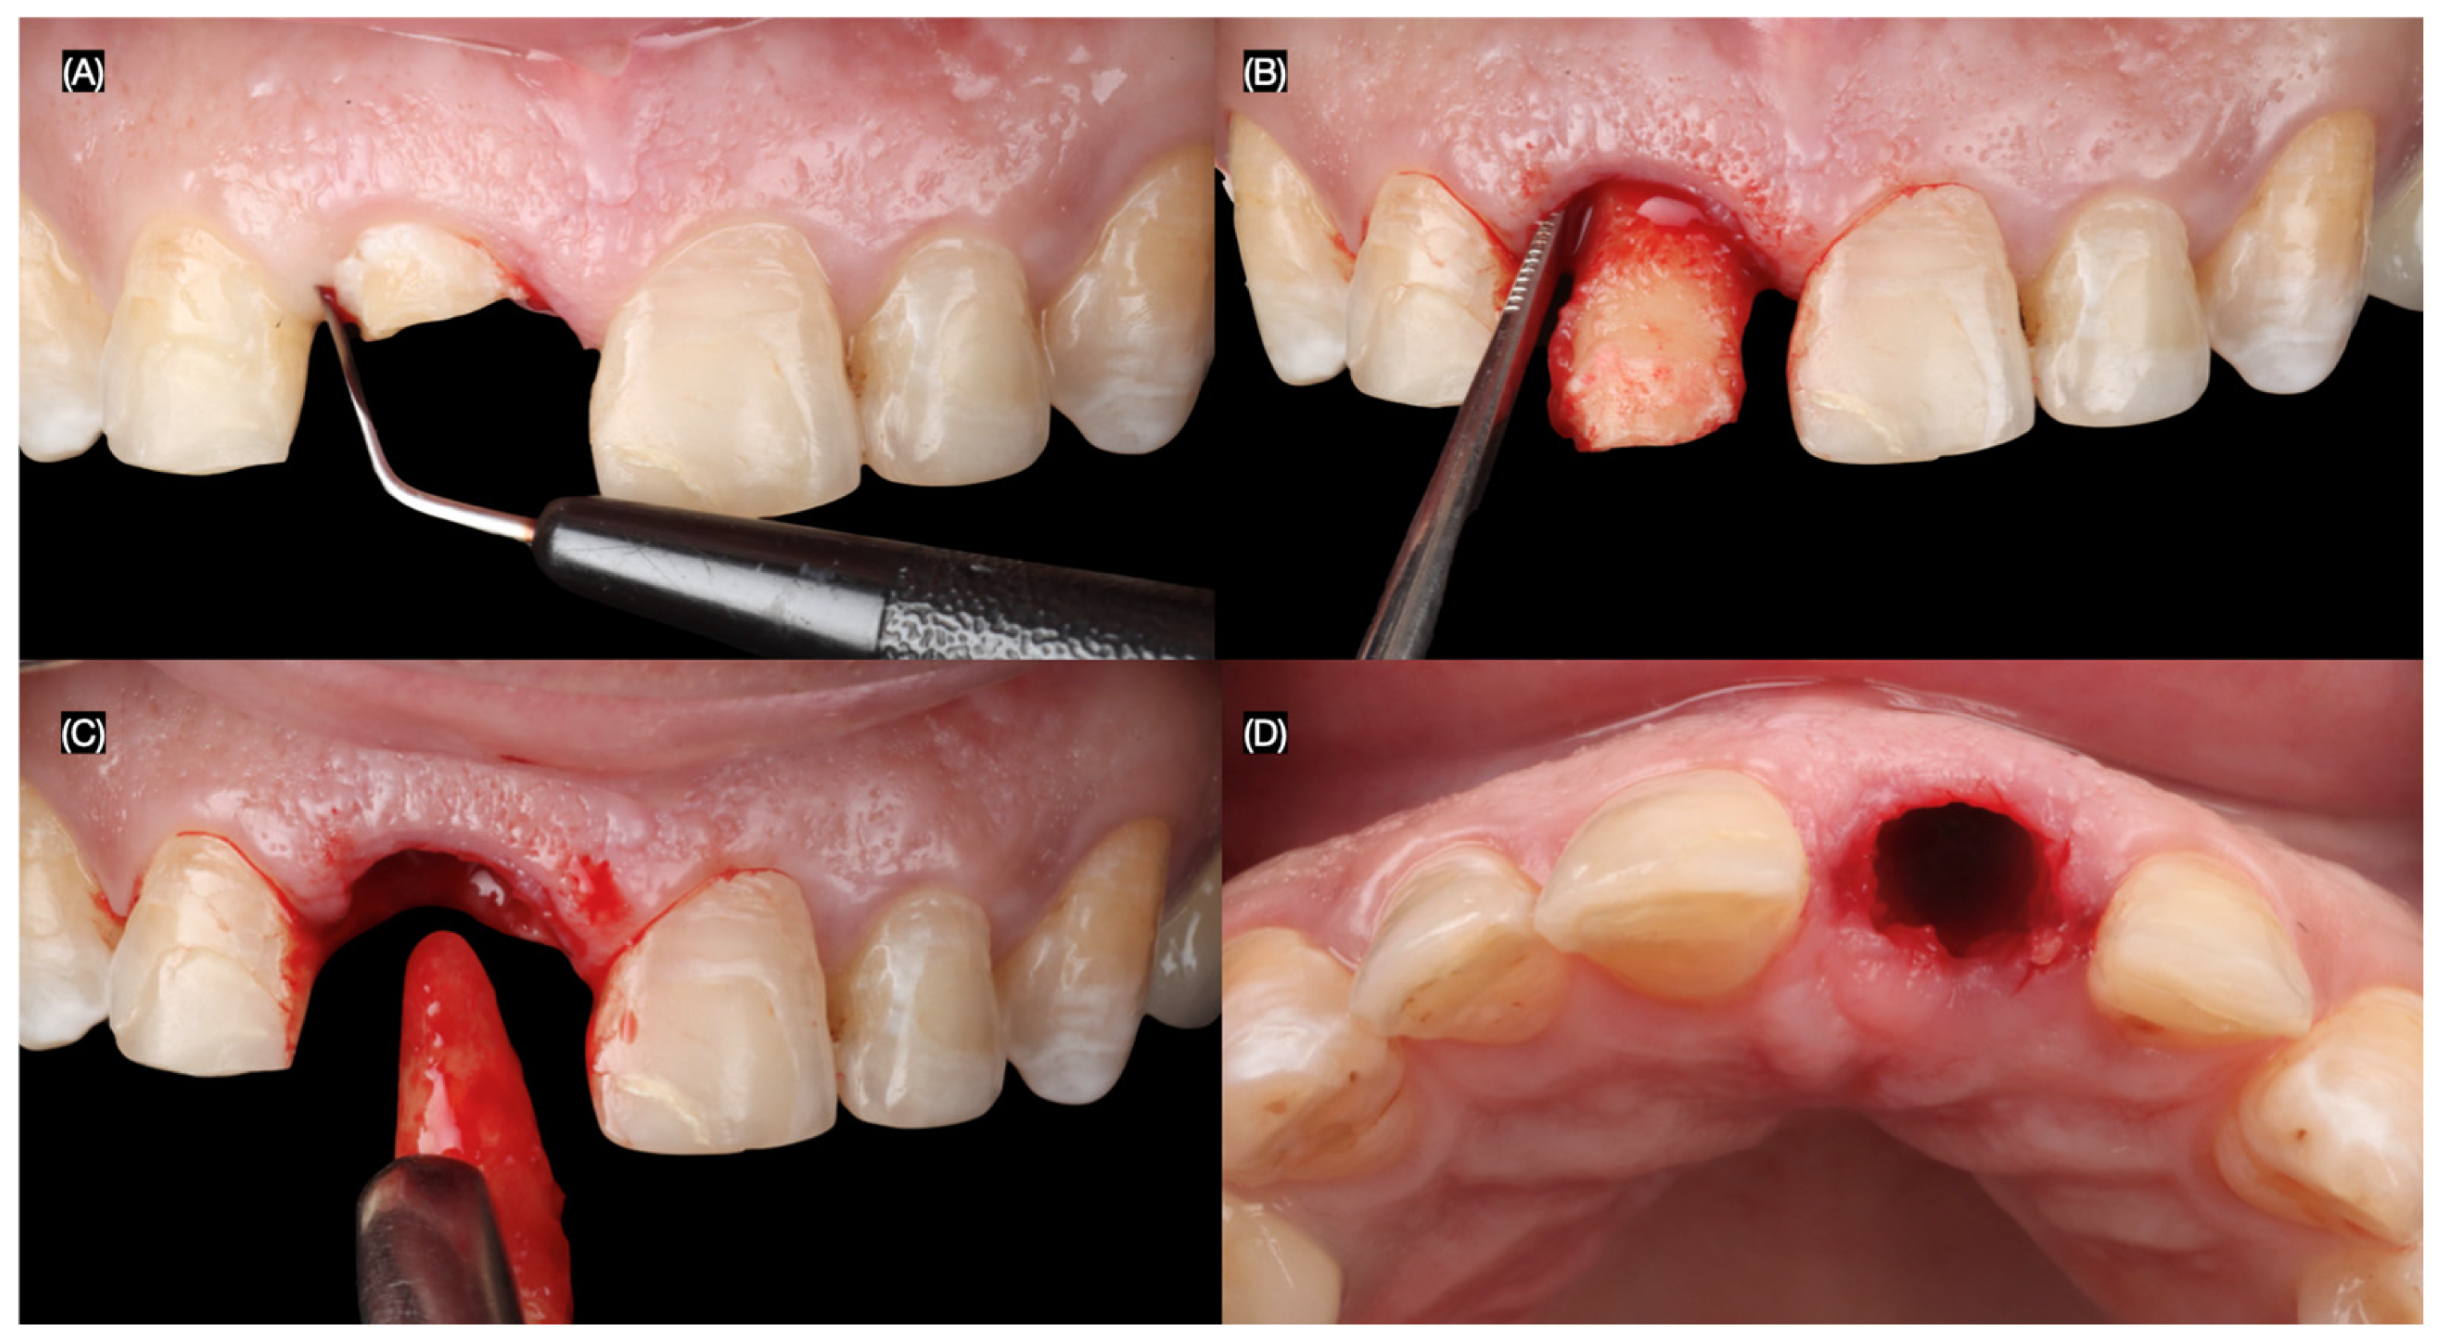

The maxillary right central incisor was extracted atraumatically, preserving the surrounding bone and soft tissues. An immediate implant (MISC C1, 3.30 mm × 13 mm, MIS Implant, Misgav, Israel) was placed using a surgical guide, ensuring precise positioning and primary stability (Figure 4 and Figure 5).

Figure 4.

Flapless atraumatic tooth extraction. (A) Desmotomes insertion, (B) luxation of root, (C) extraction, and (D) incisal view after extraction.

Figure 5.

Implant placement. Implant surgical guide: (A) incisal and (B) frontal view, (C) initial pilot drilling, (D) implant placement, and implant placed (E) with and (F) without guide incisal view.